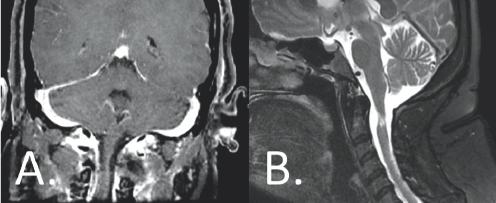

The surgery was performed with Isabella in the prone position. Blood pressure was carefully managed by the anesthesia team and neuro-monitoring was used to optimize safety. Following exposure and boney removal, Dr. Forbes meticulously dissected the tumor free from the spinal cord under magnification and removed it without complication. A tissue sample was sent to pathology, which confirmed the tumor was a benign neurofibroma. Isabella did extremely well following the surgery. Shortly after the procedure, she began to notice the strength in her extremities was improving. At her one-year follow-up visit with Dr. Forbes, she had regained a great deal of strength and was now able to ambulate without using a cane. Repeat MR imaging did not show any evidence of residual or recurrent tumor tissue (Figure 4.2); other images showed that her spinal column remained perfectly stable. At this visit, Isabella happily reported that she was now able to enjoy hikes and other outdoor activities with her young daughter for the first time in many years.

(Left) Gray and white color variations are surrounded by a gray outline. There is a gray colored column attaching a large gray space to the bottom of the image. (Right) A light grey vertical column is shown surrounded by white coloration from the bottom to the top of the image. There are other gray structures present, all of which are enclosed by a dark gray outline.

FIGURE 4.2 Coronal, T1-weighted, post-contrast (A) and sagittal, T2-weighted (B) imaging demonstrates no evidence of residual or recurrent tumor one year following resection. All mass effect has been relieved, and the spinal cord has re-expanded.